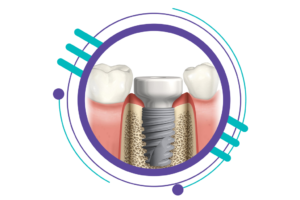

اگر بهدنبال آشنایی با مراحل ایمپلنت دندان هستید، این مطلب دقیقاً برای شماست. در اینجا نه تنها به توضیح سختترین مرحله ایمپلنت پرداختهایم، بلکه تمامی مراحل کاشت دندان ایمپلنت را بهطور کامل و بهصورت واضح شرح میدهیم

مراحل ایمپلنت دندان چیست؟

مراحل ایمپلنت دندان بهطور کلی در هفت مرحله اصلی انجام میشود. البته بسته به وضعیت فک بیمار و نیاز به درمانهای تخصصی مانند پیوند استخوان، ممکن است برخی مراحل اضافی نیز به این فرآیند افزوده شود. در اینجا به طور خلاصه، مراحل اصلی کاشت دندان ایمپلنت را معرفی میکنیم:

نکته مهم این است که انجام دقیق و کامل مراحل ایمپلنت دندان توسط پزشک باتجربه و متخصص ایمپلنت، در دوام و ماندگاری ایمپلنت دندان تاثیر بالایی دارد. در ویدئو زیر مراحل ایمپلنت دندان تصویری(فیلم ایمپلنت دندان و فیلم مرحله دوم ایمپلنت) نشان داده شده است.

سومین گام از مراحل ایمپلنت دندان، کاشت فیکسچر است که پایه یا ریشه دندان مصنوعی محسوب میشود. در این مرحله، دندانپزشک شکافی در لثه ایجاد کرده و فیکسچر را در استخوان فک قرار میدهد. این پایه بهطور طبیعی با استخوان جوش میخورد (اوسیانتگراسیون). کاشت فیکسچر یکی از مراحل حساس ایمپلنت است و دقت بالا برای موفقیت آن ضروری است.

از طرفی، تیتانیوم ماده ای سازگار با استخوان است و با استخوان فک جوش خورده و یک ساختار هماهنگ و تقریباً مشابه ریشه دندان را ایجاد می کند. بعد ازفرآیند جوش خوردن، تاج(پروتز) و اباتمنت قرار داده می شود تا امکان جویدن به صورت طبیعی ایجاد شود و دندان شما کامل شود. مراحل ایمپلنت دندان جلو شامل سه قسمت است که بهصورت زیر تعریف شده است.

کاشت دندان(فیکسچر)

ایمپلنت دندان از تیتانیوم تشکیل می شود که از طریق جراحی در استخوان فک در محل دندان از دست رفته قرار داده می شود.

اباتمنت

اباتمنت از جنس تیتانیوم، پرسلین یا روکش طلا است و شکل طبیعی دندان برای نصب تاج دندان(پروتز) را می سازند. در طول فرایند کاشت ایمپلنت، اباتمنت یا پایه دندان به کمک یک پیچ نصب میشوند. اباتمنت نقش اتصال اصلی بین تاج(پروتز) و ایمپلنت(فیکسچر) را دارد.

تاج دندان(پروتز)

در ساخت تاج دندان(پروتز) از پرسلین به همراه آلیاژ دندان به صورت تمام پرسلین یا تمام فلز استفاده می شود. تاج به اباتمنت متصل یا پیچ میشود. سوراخ پیچ با یک ماده همرنگ دندان پر می شود تا ظاهر آن طبیعی به نظر برسد.